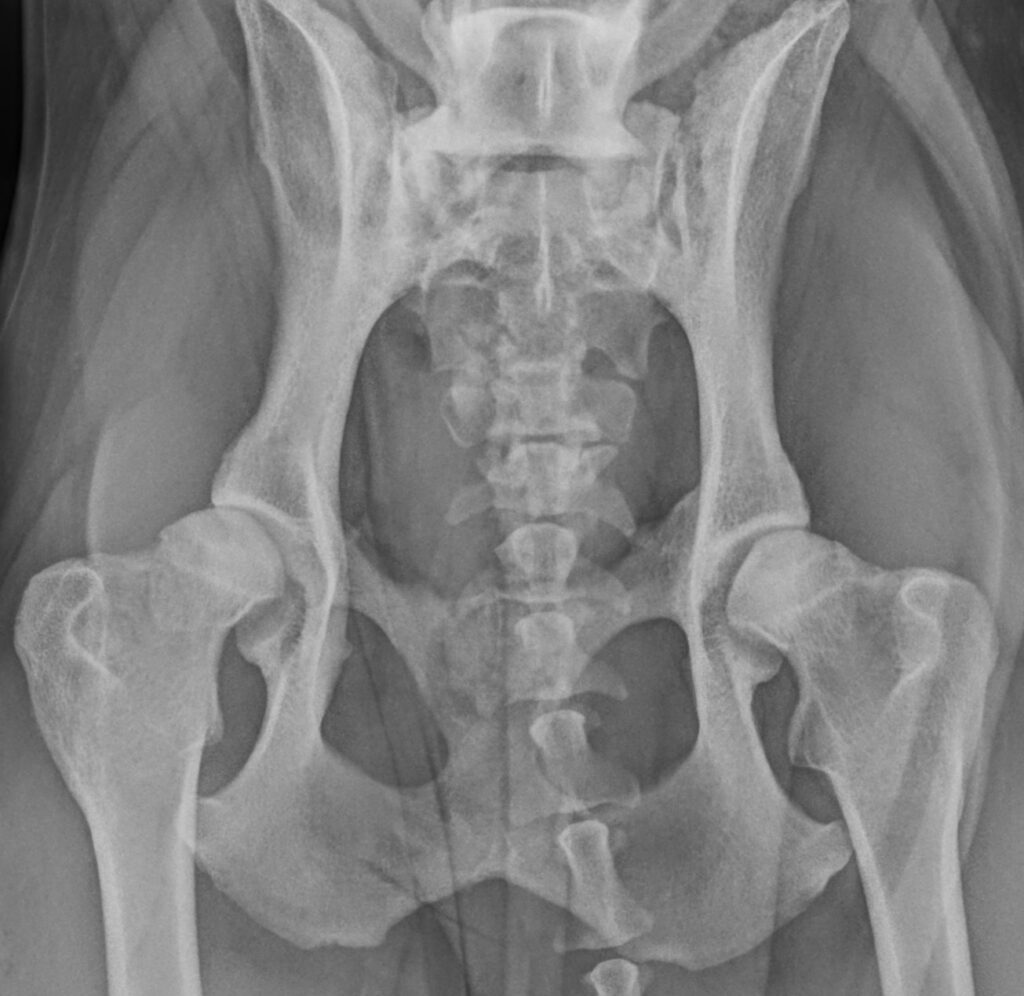

Understanding the hip joint

• Normal hip: a well-shaped femoral head (ball) sits snugly in the pelvis (socket), allowing smooth, even weight-bearing.

• Dysplastic hip: a shallow socket or deformed femoral head causes uneven loading, inflammation, and eventually arthritis.